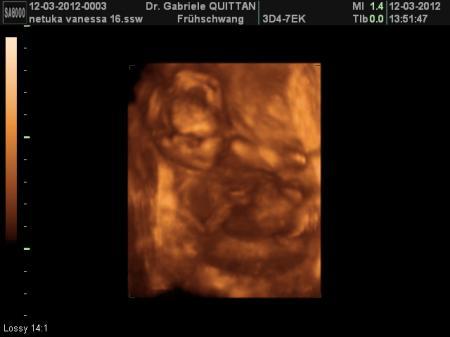

mal was von unserem buben :-)

hier winkt er gg